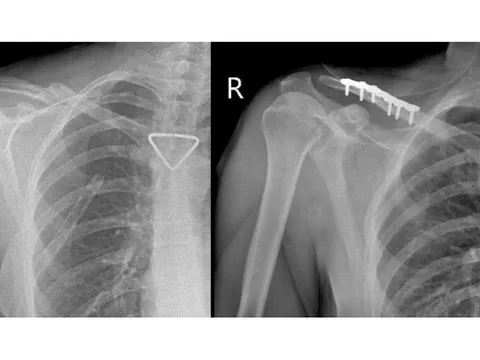

Ban đào hồng là một trong những dấu hiệu của bệnh giang mai bẩm sinh. Ảnh minh họa